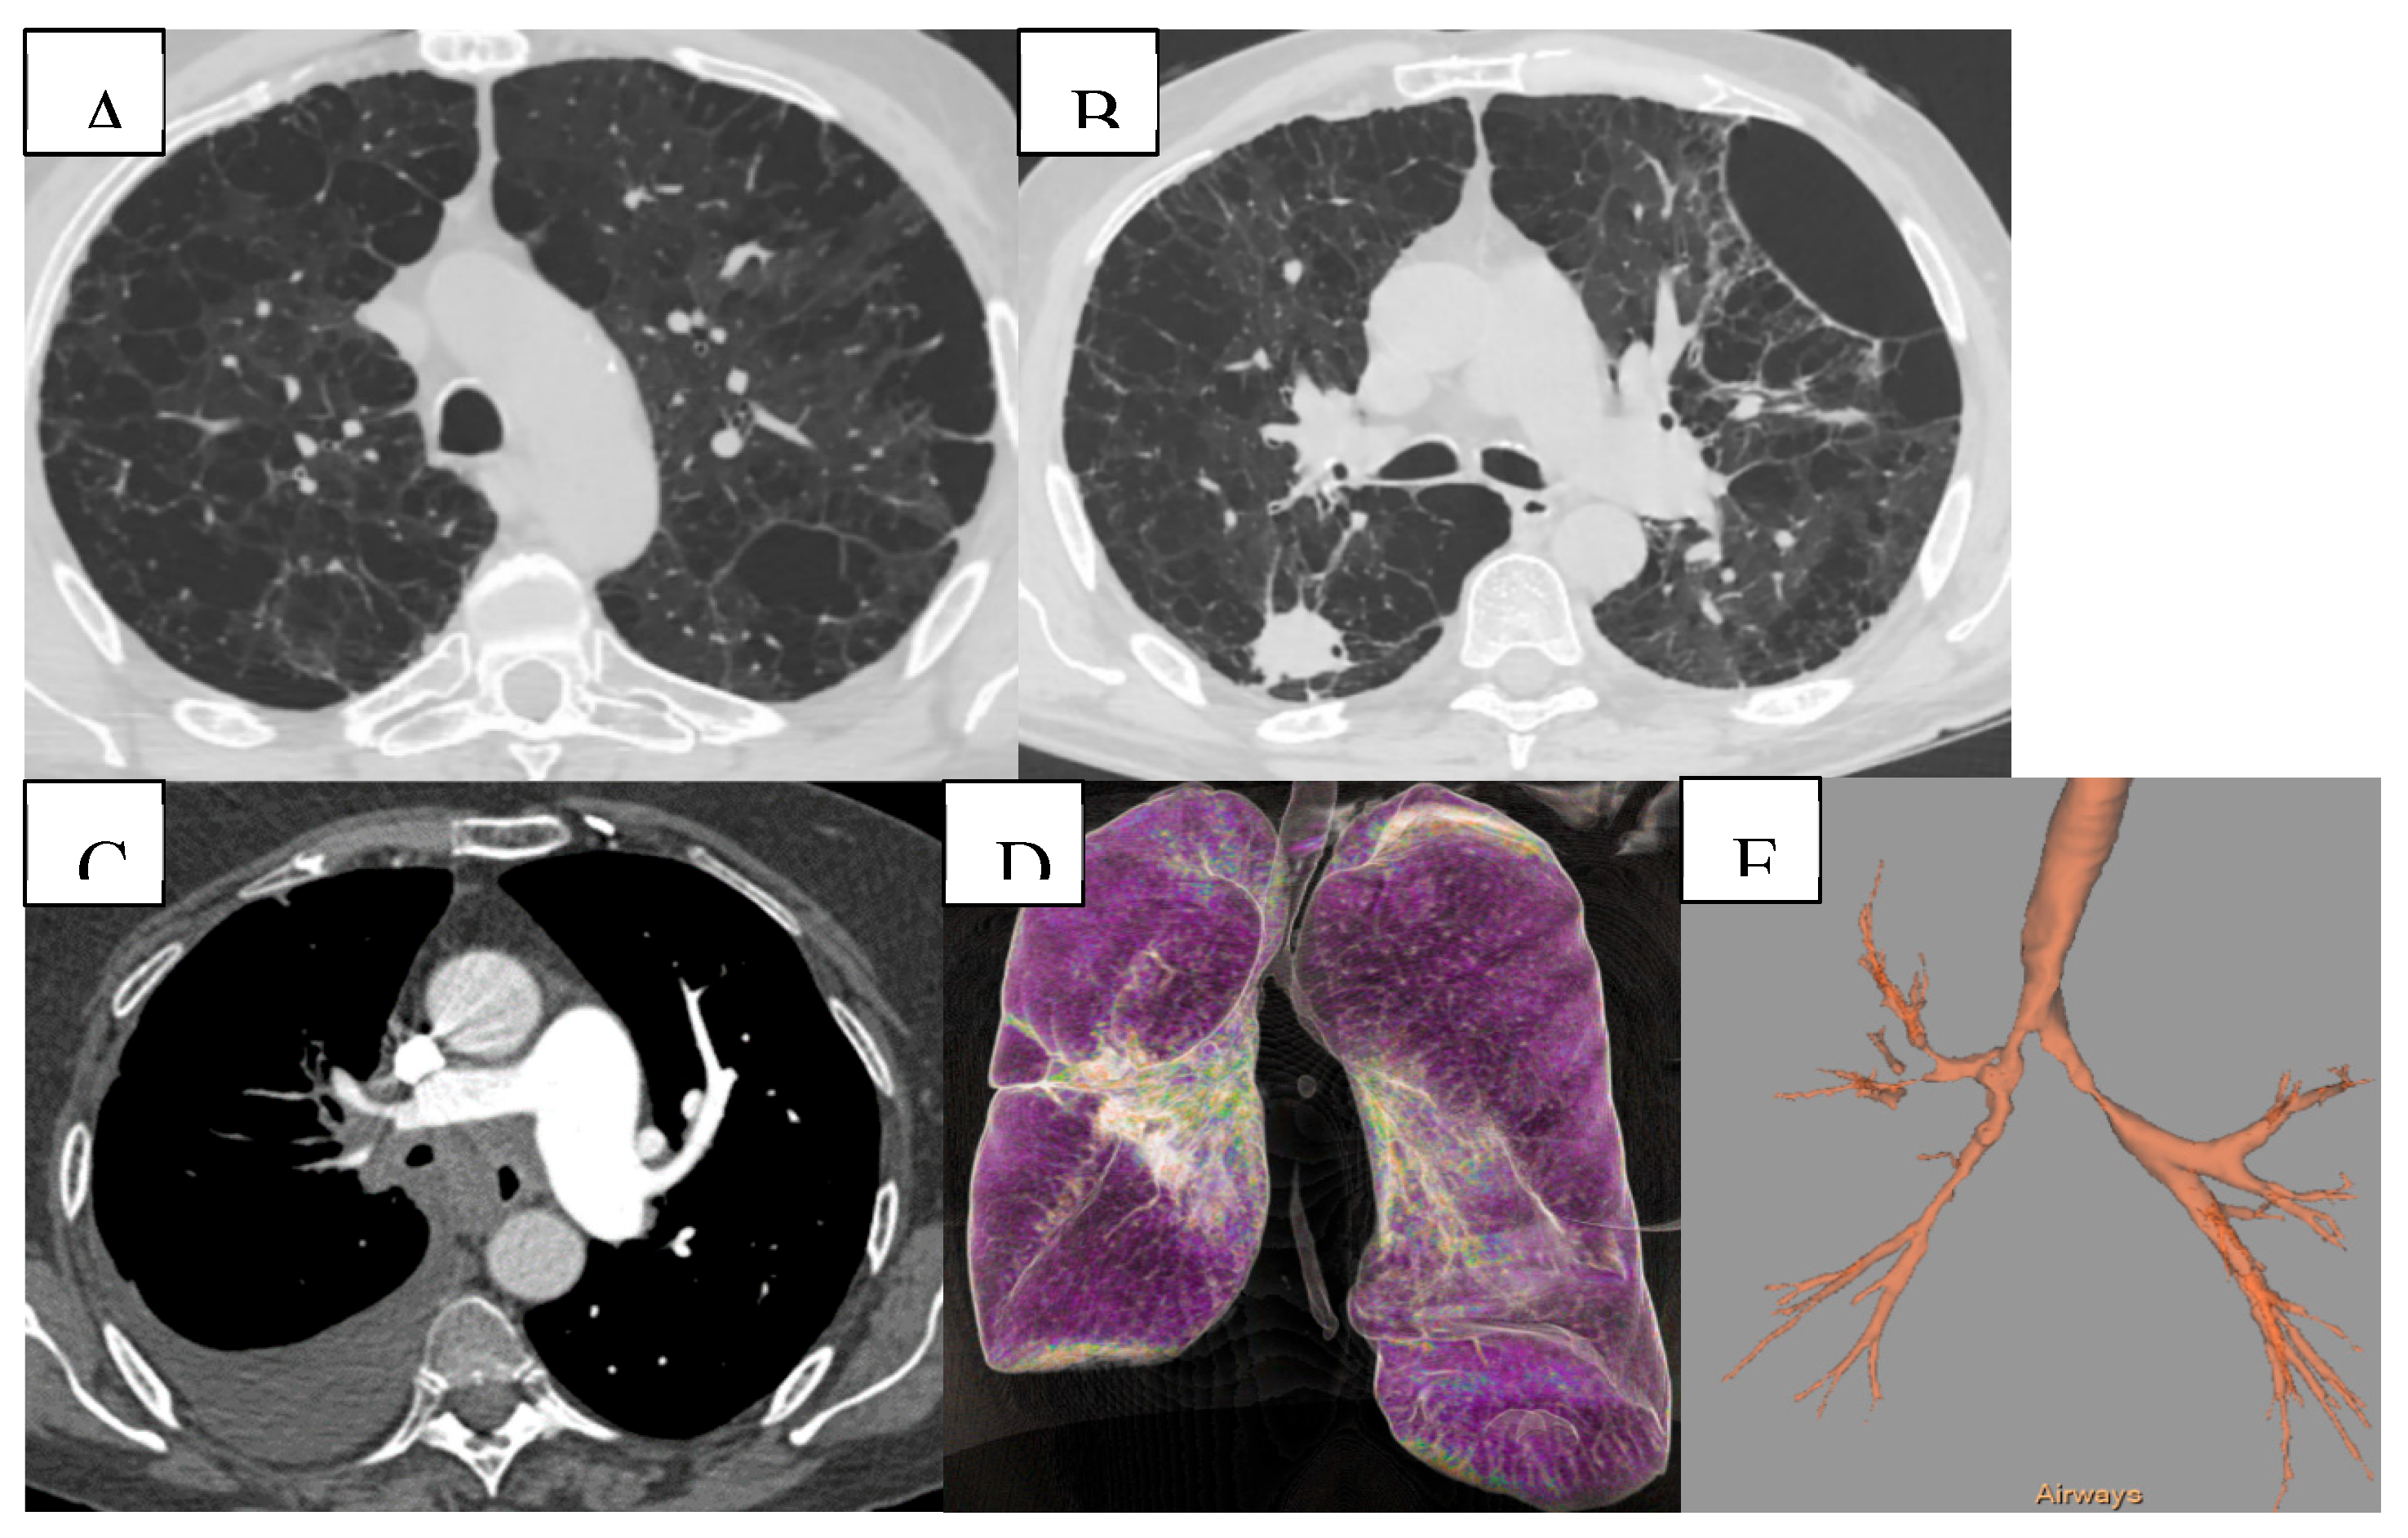

Chest computed tomography (CT) is a non-invasive imaging modality that offers valuable insight into structural and pathophysiological pulmonary parameters, enhancing the understanding of disease variability and further characterizing COPD phenotypes, such as emphysema, airway disease, and/or air trapping.16 Quantitative CT evaluation can effectively identify emphysema. The visual classification system from the Fleischner Society grades the severity of parenchymal (nonparaseptal) emphysema as trace, mild, moderate, confluent, and advanced destructive emphysema, as well as paraseptal and panlobular emphysema. Quantitative CT evaluation can affectively identify emphysema and visualize different morphological patterns, as shown in Figure 2.

Figure 2. Quantitative and volumetric HRCT assessment of emphysema. (A-C) Axial CT scans demonstrating paraseptal and centrilobular emphysema. (D-F) Three-dimensional segmentation and lobar volumetry for emphysema quantification. Computed tomography (CT) provides detailed evaluation of emphysema distribution and burden in patient with COPD. (G-H) Voxels with attenuation values below a predefined threshold (typically set at -950 HU) are classified as emphysematous. This threshold facilitates the segmentation of lung tissue into emphysematous and non-emphysematous regions, thereby enabling a quantitative assessment of the proportion of lung volume affected by emphysema.